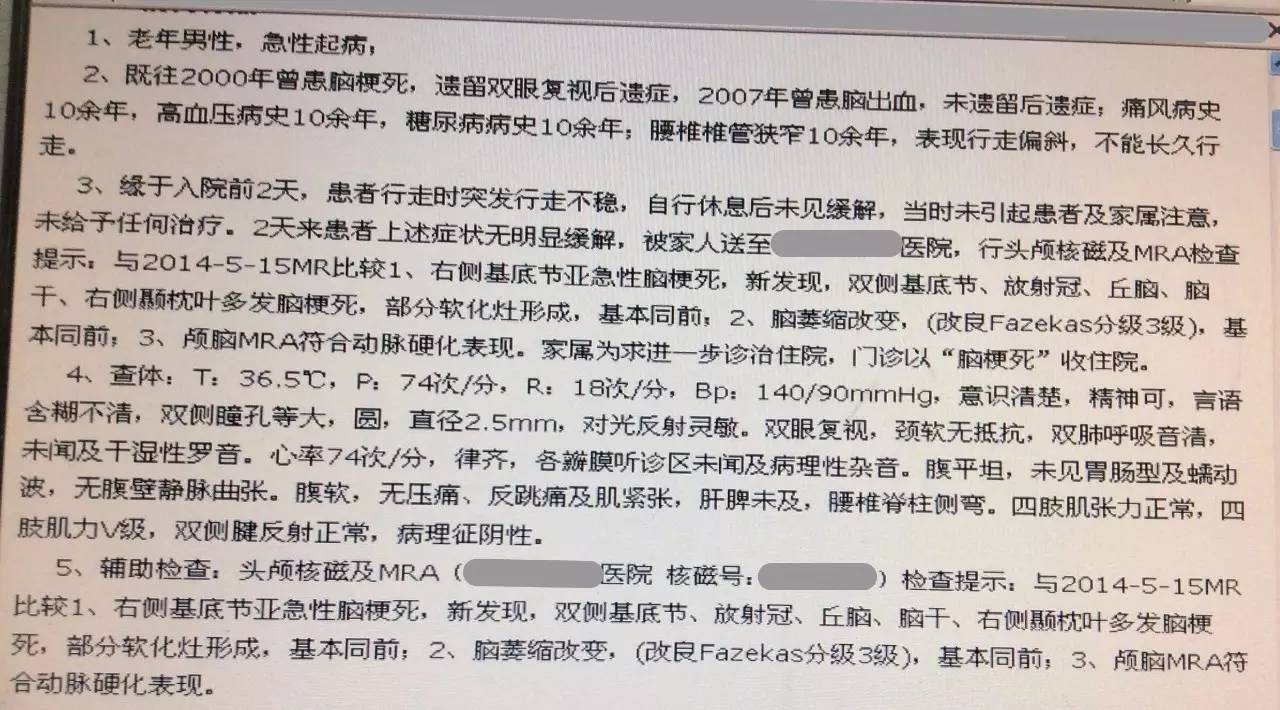

患者:男,47岁,主因“突发行走不稳2天”入院。

现病史:患者2天前无明显诱因突发行走不稳,自行休息后未见缓解,未予以治疗。2天来上述症状无明显缓解,就诊于我院,行头MRI+MRA检查示多发脑梗死、脑萎缩、颅内动脉硬化。家属为求进一步诊治收入住院。

既往:脑梗死病史16年,遗留双眼复视;脑出血9年,未遗留后遗症;痛风病史10年;高血压病史10年;糖尿病病史10年;腰椎椎管狭窄10年,表现行走偏斜,不能长久行走。

查体:生命体征平稳,神清,言语欠流利,双瞳孔正大等圆,光反射灵敏,脑神经(-)。四肢肢体肌力5级,感觉共济系统查体未见异常,四肢腱反射正常,双侧病理征未引出。颈软,无抵抗。

辅助检查:

2016-3-6 头MRI+MRA示右侧基底节亚急性脑梗死;双基底节、放射冠、丘脑、脑干、右侧颞枕叶多发脑梗死,部分软化灶形成;脑萎缩改变;MRA符合动脉硬化改变。

患者目前应用阿司匹林100mg/d,硫酸氢氯吡格雷75mg/d,阿托伐他汀钙片20mg/d治疗,系统内科治疗后患者双下肢行走不稳症状较前明显改善。但患者近三日出院发热,考虑肺部感染给予抗生素治疗,于2016-3-16 15:30出现言语不能及进食呛咳。MRI检查提示:双侧基底节、放射冠急性/亚急性腔隙性脑梗死。患者出现新鲜梗死,请帮助分析梗死原因,及下一步诊治方案。